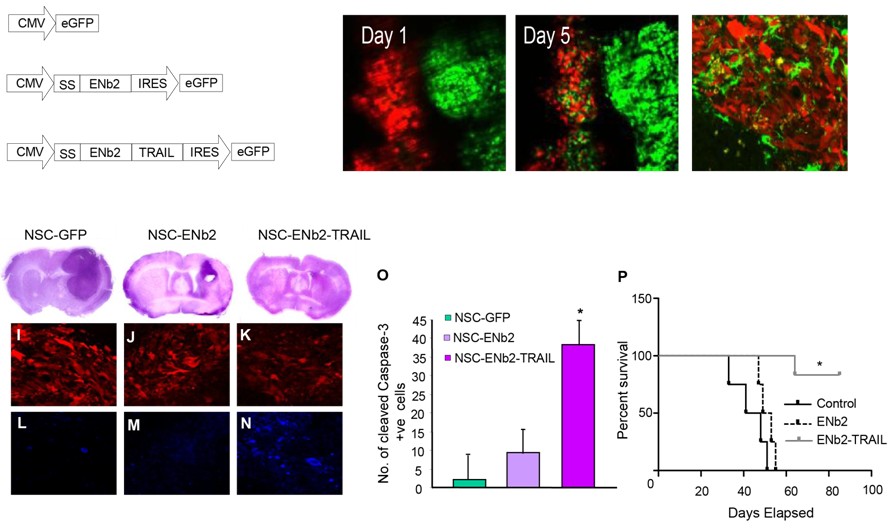

Proteome-wide search reveals multiple new +TIPs

Jiang K, Toedt G, Montenegro Gouveia S, Davey NE, Hua S, van der Vaart B, Grigoriev I, Larsen J, Pedersen LB, Bezstarosti K, Lince-Faria M, Demmers J, Steinmetz MO, Gibson TJ, Akhmanova A.

A Proteome-wide Screen for Mammalian SxIP Motif-Containing … Read more